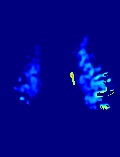

Accurate infarct segmentation in non-contrast CT (NCCT) images is a crucial step toward computer-aided acute ischemic stroke (AIS) assessment. In clinical practice, bilateral symmetric comparison of brain hemispheres is usually used to locate pathological abnormalities. Recent research has explored asymmetries to assist with AIS segmentation. However, most previous symmetry-based work mixed different types of asymmetries when evaluating their contribution to AIS. In this paper, we propose a novel Asymmetry Disentanglement Network (ADN) to automatically separate pathological asymmetries and intrinsic anatomical asymmetries in NCCTs for more effective and interpretable AIS segmentation. ADN first performs asymmetry disentanglement based on input NCCTs, which produces different types of 3D asymmetry maps. Then a synthetic, intrinsic-asymmetry-compensated and pathology-asymmetry-salient NCCT volume is generated and later used as input to a segmentation network. The training of ADN incorporates domain knowledge and adopts a tissue-type aware regularization loss function to encourage clinically-meaningful pathological asymmetry extraction. Coupled with an unsupervised 3D transformation network, ADN achieves state-of-the-art AIS segmentation performance on a public NCCT dataset. In addition to the superior performance, we believe the learned clinically-interpretable asymmetry maps can also provide insights towards a better understanding of AIS assessment. Our code is available at https://github.com/nihaomiao/MICCAI22_ADN.